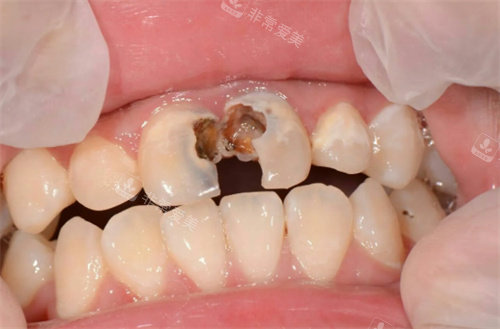

牙齿龋坏

牙齿龋坏不同程度图片